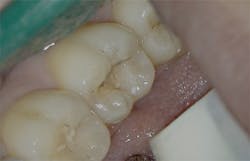

Figure 3: Class I cavity prep after laser. Photo courtesy of Jeff Rhode, DDS.

Figure 4: Class V pre-op lesion. Photo courtesy of Jeff Rhode, DDS.

Figure 5: Class V cavity prep with laser. Photo courtesy of Jeff Rhode, DDS.

Figure 6: Class V restoration. Photo courtesy of Jeff Rhode, DDS.

For the same reasons, the 10.6-micron CO2 laser has also been shown to damage the implant surface and increase the temperature of the adjacent hard and soft tissue surrounding the dental implant.4 Because of the difference in wavelength, absorption pattern, and introduction of water irrigation with the 9.3-micron CO2 laser (figure 1), it can now be used for hard-tissue applications. This laser has been used to prepare teeth for Class I–IV (figures 2–8) restorations without the concern of raising pulpal temperature and inducing necrosis. The laser has also been used as an alternative to conventional high-speed drills to prepare teeth for crowns, bridges, and veneers.